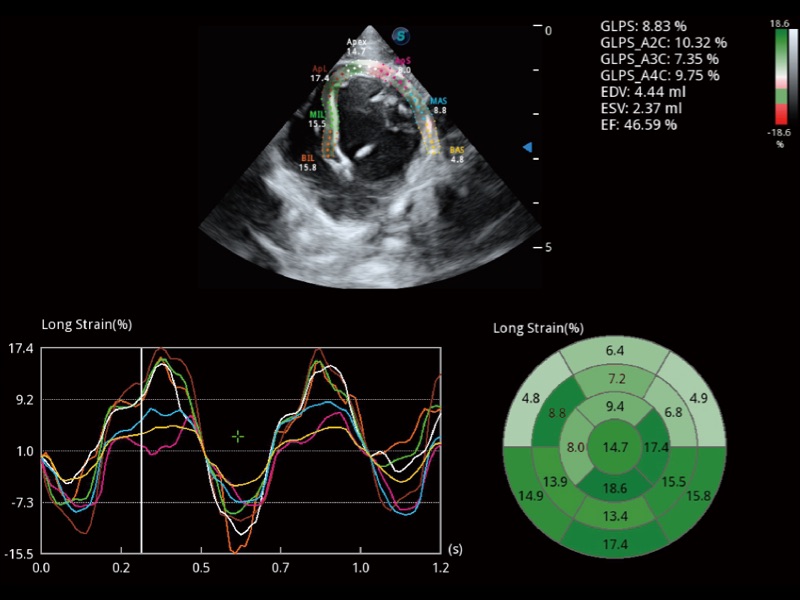

具備多種協(xié)議可選,同時(shí)支持17階段劃分法和專業(yè)的SE報(bào)告。

實(shí)時(shí)用顏色表示心肌組織運(yùn)動,觀察和定量組織的運(yùn)動情況,對快速檢測與評估心肌的灌注和活性、電傳導(dǎo)及心肌收縮和舒張功能等均能提供重要的診斷信息。